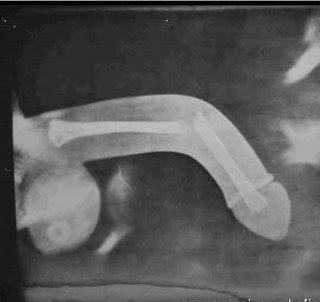

Ánimo Javi!!, te puedo decir que el que suscribe, yo mismamente, llevo 4 operaciones de esas, con una placa en L4-L5 y fijaciones con tornillos en L3-L4, porqué 4 veces? las dos primeras me tocó un residente.......para qué hablar, las dos siguientes pura mala suerte, accidente laboral, me cayó encima una tonelada de marmol, y me jodió otra vez, pero soportar los dolores, y nada mas despertar de la anestesia no tenerlos no tiene precio, de hecho estuve 10 dias en hospital invalidado totalmente con morfina y nada de nada. Yo te diría, y por la foto de la resonancia que enseñas, que estás para quirófano, pero sobretodo que sepas que no se acaba el mundo y a tirar adelante. A fecha de hoy estoy fenomenal, mas cómodo en moto que en coche, por la posición. Lo dicho, ánimo y sobretodo que lo que tenga que ser que sea rápido :) Un saludo.

En fin... si es una hernia importante como se apercia en la RM del compañero, mejor operarse antes de llegar a la atrofia muscular... la recuperación es más rápida y mejor...